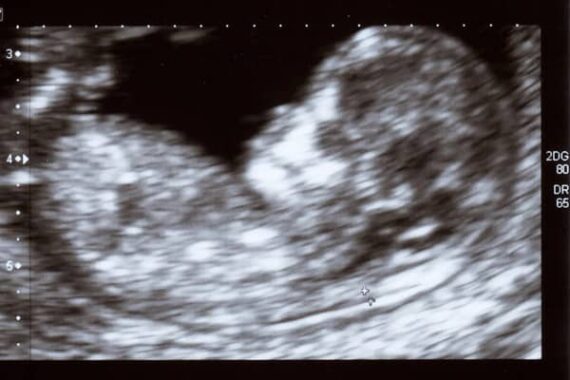

Planned Parenthood a annoncé qu’à partir du 1er octobre prochain, les avortements ne seront plus réalisés dans le Wisconsin. Cette « décision » fait suite au blocage des financements des entreprises d’avortement par l’administration Trump, blocage confirmé par une cour d’appel fédérale.

Dans un communiqué, Planned Parenthood of Wisconsin a déclaré : « En attendant, nous explorons toutes les options possibles : recours aux tribunaux, interventions chirurgicales et engagement citoyen. » « Toutes les options possibles », oui, pour continuer de s’emparer de la détresse souvent induite de jeunes femmes afin de continuer de promouvoir la culture de mort.